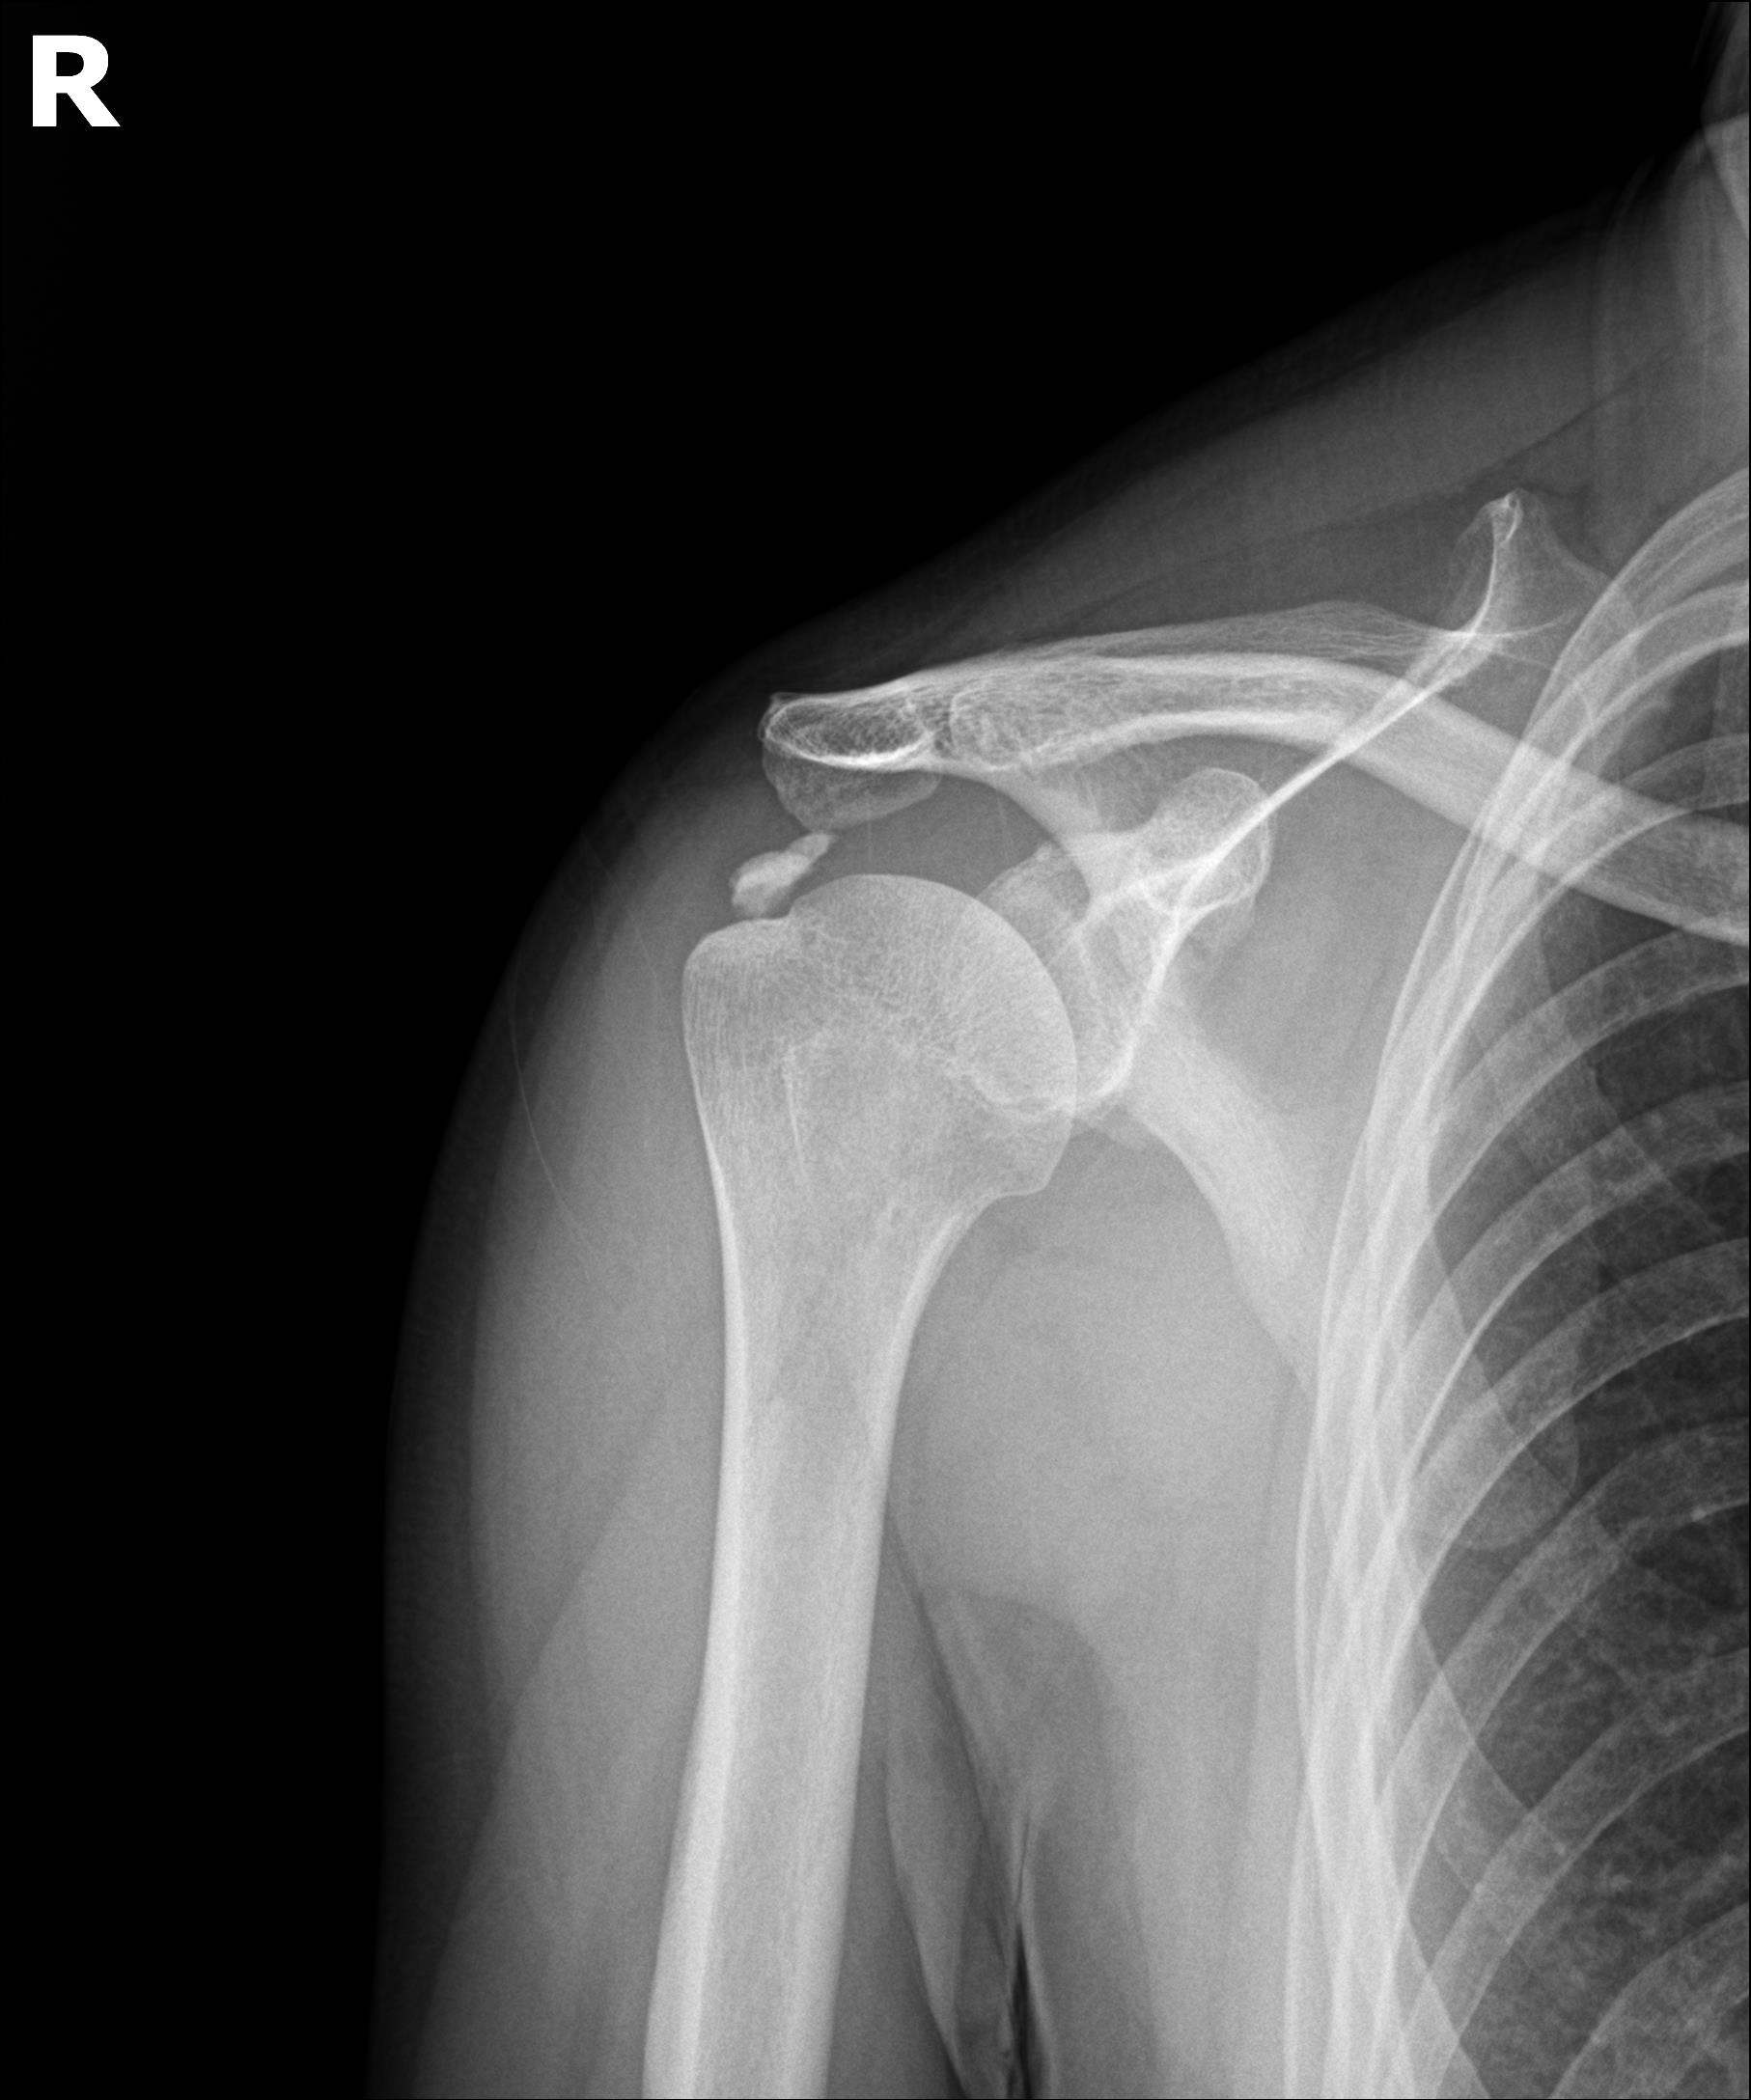

케이스 1: 형성기 단단한 석회 (1회 제거)

환자: 50대 남성, 우측 어깨 통증 8개월

시술 전:

X-ray에서 약 1.5cm 크기의 석회 확인

형성기 석회 (매우 단단)

타 병원에서 "수술 권유" 받음

시술 후:

1회 분쇄흡입술로 완전 제거

시술 직후 X-ray에서 석회 없음 확인

플래티넘에서의 치료

진단:

X-ray: 약 1.3cm 석회 (휴지기)

초음파: 석회 주변 인대 염증 소견

시술:

상완신경총 차단 마취

석회분쇄흡입술 시행

시술 시간: 35분

결과:

시술 직후 X-ray에서 석회 완전 제거 확인

기존 인대 염증은 재생주사로 추가 치료